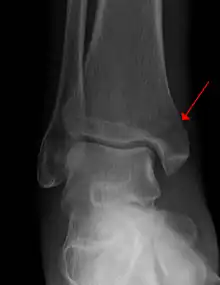

| Example of an intraarticular fracture of the medial malleolus extending in the talocrural ankle joint | |

An intraarticular fracture is a bone fracture in which the break crosses into the surface of a joint. This always results in damage to the cartilage.[1] Compared to extraarticular fractures, intraarticular have a higher risk for developing long-term complications, such as posttraumatic osteoarthritis.[2]